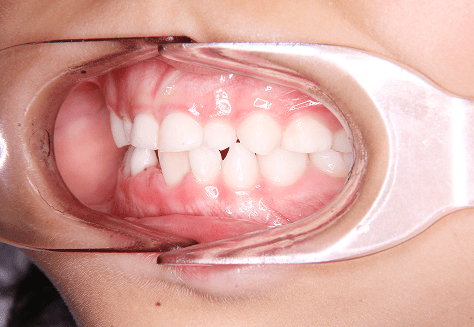

M.M

治療前

治療後

主訴

嚙み合わせが悪い。八重歯が気になる。

診断

叢生・反対咬合

年齢/性別

10代/女性

抜歯部位

非抜歯

使用装置

インビザラインファースト→インビザラインフェーズⅡ(部分的にワイヤーにて処置)

保定装置

上下ビベラリテーナー

診察料金

ファースト時:0円×16回

フェーズⅡ時:5,500円×9回

ワイヤー併用時:8,800円×2回 -

治療期間

2年7カ月